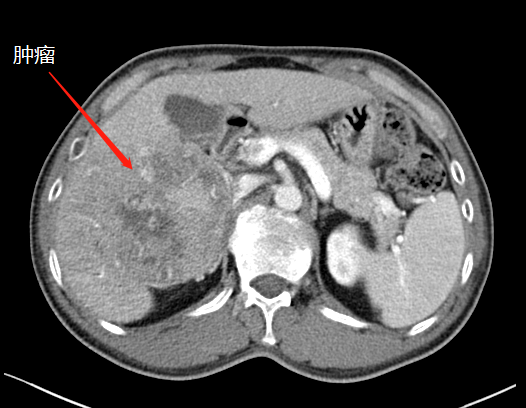

左肝增生,第二次手術切除腫瘤

二次手術完整切除腫瘤

于是,專家團隊便于10月中旬為患者實施了第二階段腫瘤切除術,在此過程中,由于患者同時合并腹繭癥,通過第一次手術的刺激腹腔內(nèi)粘連非常嚴重,手術遭遇了巨大的困難,最后經(jīng)過近7小時左右的艱苦奮戰(zhàn),攻堅克難,終于完整切除了患者右肝的巨大腫瘤,手術取得了成功,患者重獲新生。